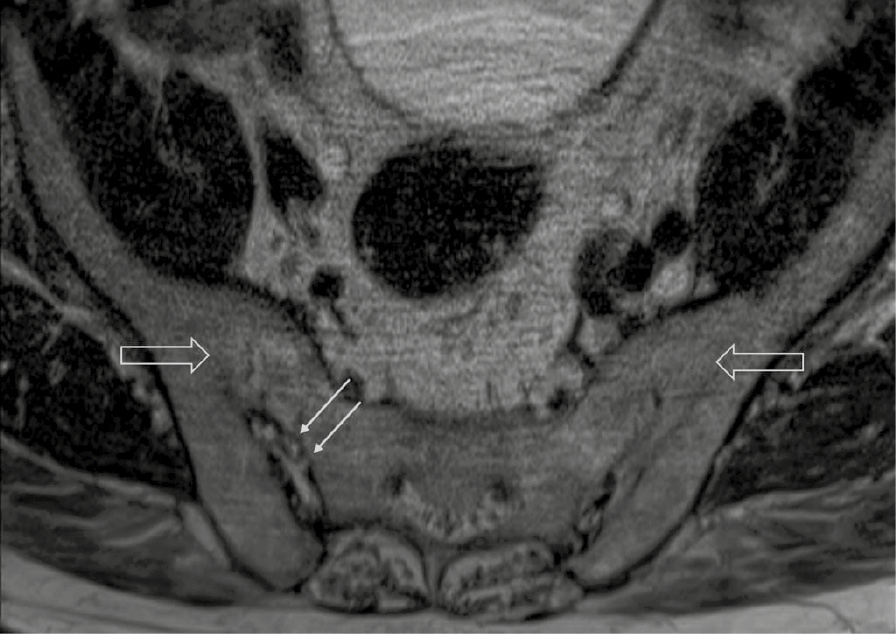

При компьютерной томографии органов грудной клетки данных за «свежие» очаговые и инфильтративные изменения не получено. Увеличения лимфатических узлов подмышечных областей, средостения, корней легких не выявлено. Отмечался усиленный грудной кифоз, обызвествление передней продольной связки, на всем уровне исследования определялись передне-боковые спондилофиты, а также анкилоз большинства реберно-поперечных суставов. По данным рентгенографии кистей (рис. 1, 2) и стоп (рис. 3, 4) диагностированы признаки эрозивного артрита, анкилоз суставов запястья. По данным МРТ крестцово-подвздошных суставов (КПС) определялся неравномерный анкилоз КПС, хрящи по суставным поверхностям неравномерной толщины, примерно на половине протяжении сустава отсутствуют, «суставной промежуток» облитерирован. Неравномерность и нечеткость контура суставных поверхностей за счет множества краевых эрозий справа, единичных – слева, с наличием остеокластоза, в нижнем отделе слева по смежным отделам определяются участки трабекулярного отека, данная находка клинически интерпретирована как двусторонний активный сакроилиит (рис. 5, 6).

Рис. 1. Рентгенограмма левой кисти в прямой проекции. Краевые эрозии суставных поверхностей первого пястно-фалангового сустава (тонкие стрелки), сужение суставных щелей суставов запястья с формированием анкилозов (толстая стрелка)

В возрасте 40 лет присоединились жалобы на симметричные воспалительные боли в лучезапястных суставах и мелких суставах кистей, резкое снижение объема движения в лучезапястных суставах. При осмотре пациента выявлено: число болезненных суставов – 7, число припухших суставов – 4, положительный симптом поперечного сжатия кистей и стоп, ульнарная девиация мелких суставов стоп. Резко сниженный объем движения в лучезапястных суставах обеих кистей. По данным рентгенологического обследования зафиксированы типичные изменения для РА: резкое неравномерное выраженное сужение суставных щелей, субхондральный склероз в лучезапястных суставах, анкилоз в суставах запястья, пястно-запястных, пястно-фаланговых и межфаланговых суставах. Краевые эрозии оснований основных фаланг двух пальцев; участки кистовидной перестройки костной ткани. Локальное утолщение мягких тканей. При лабораторном обследовании пациента отмечен положительный ревматоидный фактор, высокий титр антицитруллинированных антител, повышение острофазовых белков.